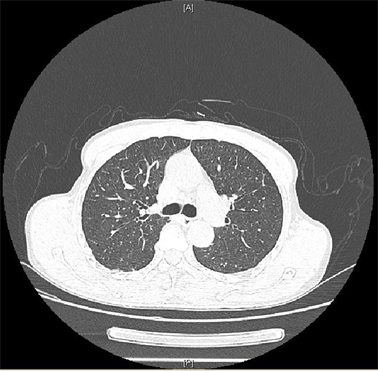

纤支镜下可观察到在隆突两侧各有一支气管开口,隆突上方右侧有一右肺上叶气管开口,考虑为TB(见图1)。查看患者术前CT示:在CT图像165(image,im165)可见右肺上叶开口于主气道(见图2),在im182可见正常的左右主支气管开口于主气道(见图3),证实该患者为TB。

3.jpg

图3 CT,im182,正常的左右主支气管开口